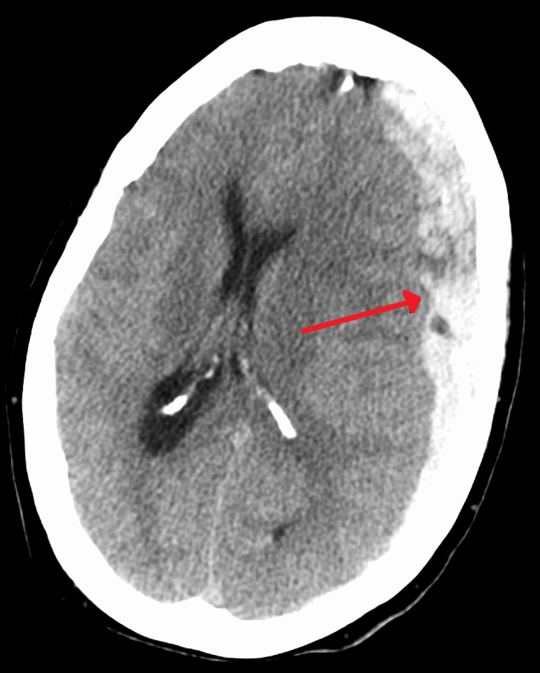

Example 2

Diagnosis

Subdural Haematoma